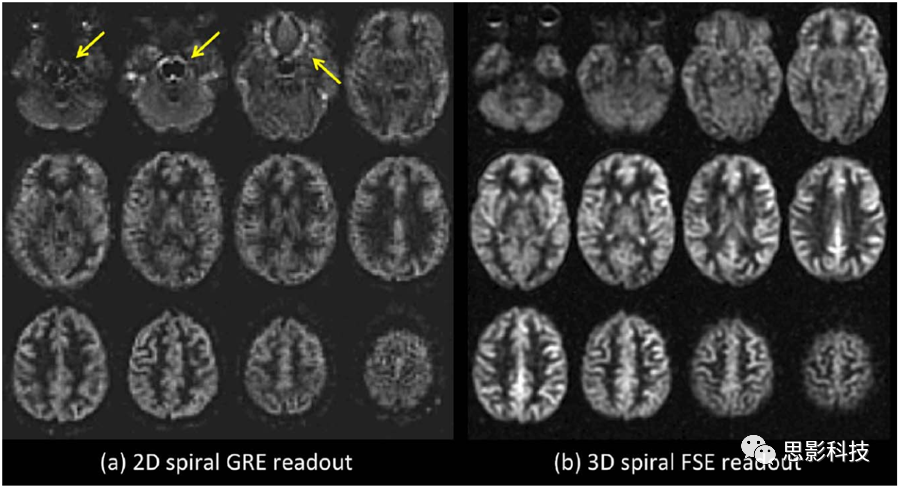

对于ASL的读出模式,三维节段式序列是其首选方案,因为其在每个TR下都施加了一次脉冲激励,对于背景抑制来说这是最佳的设定,因为这种读出方式可有效提高信噪比且相对不受非共振效应的影响。当前来说单次扫描读出应是最优的首选方案,但是这些方法还没有经过严格的测试,不推荐作为一个通用的方案。多层单二维成像读出或者螺旋读出序列,因其普遍适用且不受运动伪影的影响可认为是一个可替代的三维分割序列。但是相对而言,二维的成像方式也存在背景抑制效果差以及扫描时间长等问题。图5为带有2D和3D读取的ASL示例,Vidorreta等人和Nielsen and Hernandez-Garcia更详细地比较了这些方法在ASL中的应用。

Figure 5不同读出方式的比较

三维分割读取

作为默认读取方法,推荐使用三维节段方法,如快速自旋回波螺旋式K空间填充叠加方式或3D GRASE方式(一种混合采集方式)。这些方法为ASL脉冲制备的磁化强度的测量提供了接近最佳的信噪比,并且它们对场的不均匀性相对不敏感。它们在纯RARE的读取方法对T2不敏感度,并且与纯EPI或Spiral方法的时间效率之间取得了平衡的处理,从而获得了两者的大多数优点。与2D多层读数相比,这些方法可显著改善背景抑制。背景抑制技术仅在一个时间点时是最佳的,并且由于分段的3D读数在每个TR周期仅需要一次激励,因此可以对激励进行定时以提供高质量的背景抑制。优化背景抑制参数以获得最小的静态组织信号,并且应该计算标记图像和对照图像之间的复杂差异以重建ASL信号,因为接近零的幅度重建图像之间的差异会产生差异。请注意,将背景抑制用于分段3D采集对于ASL至关重要,如图6所示。分段方法需要激发之间的数据一致性,并且在没有背景抑制的情况下,与运动有关的伪影通常将主导ASL信号(如图6所示)。

Figure 6使用2d 单次扫描采集的图,以及3d分割读出图像对比

第二选择是2D单次成像方法,其可有效地应用于ASL。 EPI和螺旋方法已被广泛使用,而单次RARE和平衡SSFP也是可行的,但是不那么常见,并且这种读出方法针对ASL的测试还不够深入。对于ASL,EPI和Spiral的性能,彼此相似,但差异很小。螺旋可以缩短回波时间(TE),以减少T2 / T2 *的权重,但会产生与共振无关的模糊。 EPI具有更长的最小回波时间,但在共振偏移的情况下会表现出失真而非模糊。至于3D成像,建议在特定系统上更好地优化这两种方法中的任何一种。通常,对于单次2D读数,建议使用升序切片顺序。单次成像方法的优点之一是,它们不受运动伪影的影响。对于2D成像,背景抑制技术仅对一个或几个切片而言是最佳的。尽管这通常是一个缺点,但残留的静态组织信号可能会以两种方式使用。首先,可以使用幅度图像重建,它比复杂的重建和线圈组合要简单。第二,残留信号可以在标签与控制相减之前用于图像配准。尽管背景抑制在2D单次成像中的影响远不如3D成像中的剧烈(图6),但可以看到信号波动显著降低,尤其是在患者运动明显的情况下,建议使用背景抑制。有关其他推荐的成像参数,请参见表2。